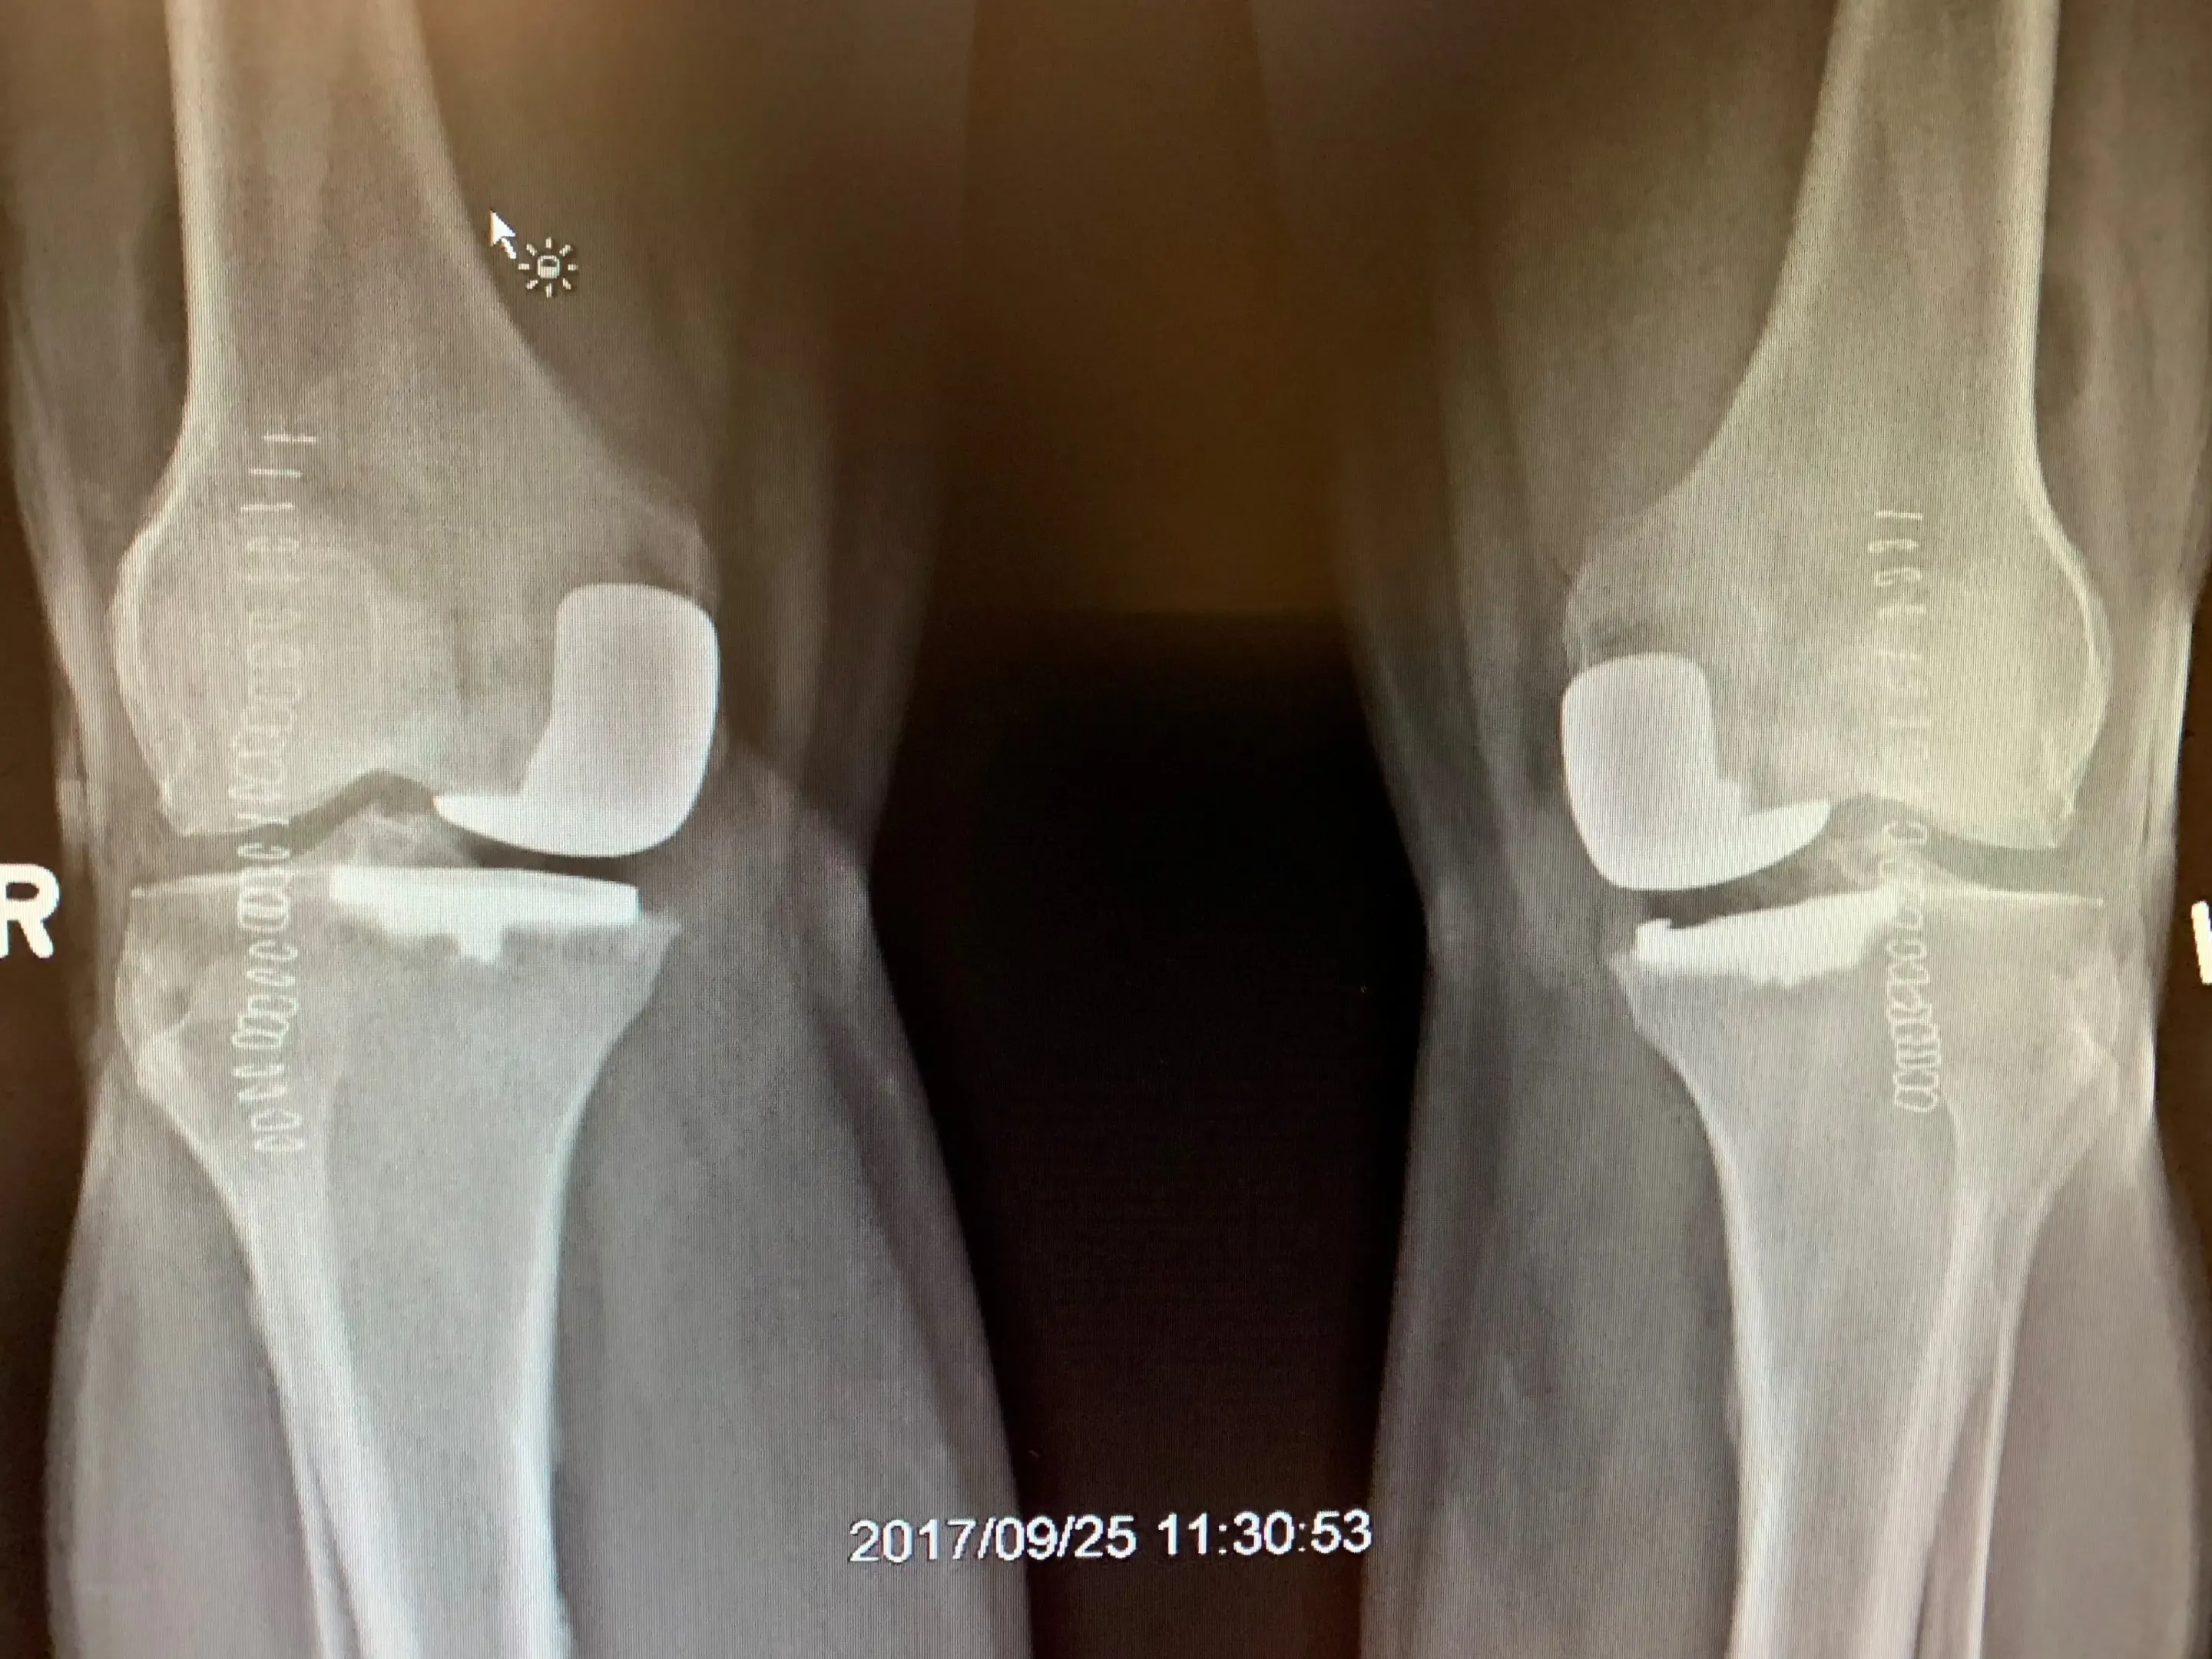

Post-op

Simultaneous bilateral Unicondylar knee replacement in a 67-year-old male.